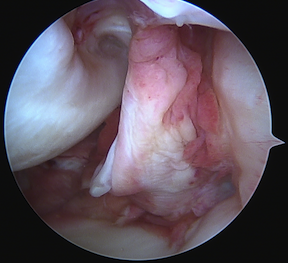

Arthroscopy

May miss tear as is extra-synovial

Acute PCL femoral avulsion

Apparent ACL laxity due to PCL tear and posterior tibial sag; ACL tension restored with anterior drawer